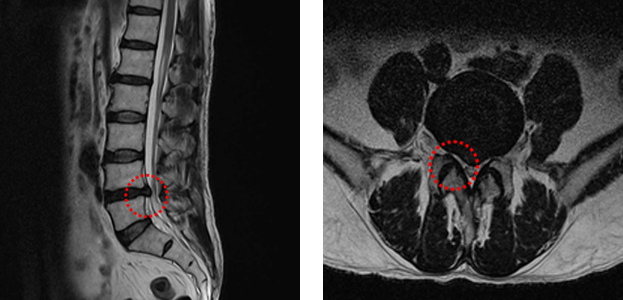

디스크환자 MRI

• 측면 MRI

• 단면 MRI